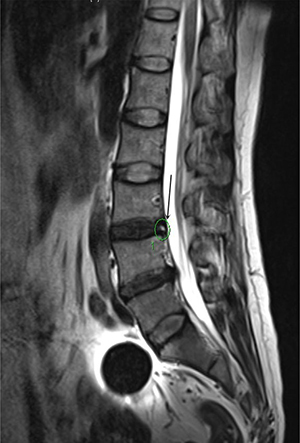

Figure 4: HIZ was presented by MR at the T2 signal (L3-4) for a 56 years old women, diagnosed with discogenic LBP for 3 years.

It is not easy to use the symptoms and clinical examinations to diagnose or localize the level of abnormality as the discogenic LBP has a somatotropic rather than dermatomal pattern of pain projection [9]. Several other modalities have been used to help the diagnosis of discogenic LBP, such as MR, CT, myelography, and X-ray [5]. The most frequent imaging modality was MR, which could provides a unique means to evaluate the morphologic status of discs. Study show that MR showed a significant correlation with the discography findings in evaluating disc degeneration as most of the discs with normal morphology on MR were also normal on discography [13]. The clinical relevance of a posterior HIZ on T2-weighted MR images represents fluid or mucoid material associated with granulation tissue and new blood vessels entrapped between torn fibers of the outer annulus or underneath the posterior longitudinal ligament complex [14]. HIZ is mainly due to mechanical fatigue loading, and inflammatory reactions associated with repair of an annular tear. For many patients, the inflammatory mediators such as TNR-α, IL-1, IL-6 released following the annular fissures [15–16] may explain the LBP and their high signal intensity on T2-weighted images. According to the results of the univariate analysis, 31 patients (51.7%) show posterior HIZ on T2-weighted MR images in the study group while only 7 patients (11.7%) in the control group show the same appearance, significant difference was detected between the two groups (t = 22.1; p = 0.00). We also confirm that high diagnostic value of HIZ were also obtained based on the results of multivariate analysis (p = 0.013) and ROC curve(AUC=0.717). So we conclude that HIZ on T2-weighted MR images is credible to forecast the discogenic LBP.

Angle motion of the lumbar spine intervertebral was measured to indicate the degree of spine instability and include angle motion and lumbar mobility [32].Two lines across the upper and lower vertebral body margin of lesion level insect and form the angle at flexion and extension position by X-ray (Phillips,Eindhoven, Netherlands), difference of the flexion and extension angle was defined as the angle motion of lumbar spine [33]. Lumbar mobility was measured by calculating the distance between upper and lower vertebral body of the lesion level at the lateral position by X-ray. The cobb angle of interest is simply the angle between the two line drew from the upper endplate of the upper body and along the lower endplate of the lower body [34]. Height of the lesion disc was measured by supine MR (Siemens,Germany). The T1 and T2 intensity images were constructed with the TE/TR of 10/500 ms and 100/2800 ms. The slice thickness was 4 mm. We performed the measurement on the T2 intensity images at the sagittal planes. The measurement of the vertical intervertebral disc lengths was performed on the mid-saggital section of the vertebral body (anterior, middle and posterior). Measurement of spinal canal dimensions of the lesion level (saggital diameter and transverse diameter) was carried out by supine MR to reflect degree of the lumbar spinal stenosis [35]. HIZ was defined as a small, round zone with limited high-intensity signals in the posterior annulus of lumbar intervertebral discs on sagittal slices of T2-weighted MR, it also represents a deep radial fissuring the annulus fibrosis of the lesion level, just as revealed by lumbar CT discography [36–39]. Modic changes are usually displayed by MR to describe the signal intensity changes of vertebral end-plate of the lesion disc [40]. Modic type 1 changes (MC1) refers to low T1 and high T2 signal, MC2 refers to high T1 and T2 signal, and MC3 refers to low T1 and T2 signal [41]. Grading of disc degeneration was assessed from T2-weighted sagittal images based on the Pfirrmann method [31]. Two independent spine surgeons performed the measurement by using Centrieity Enterprise Web V3.0 (General Electric,US).